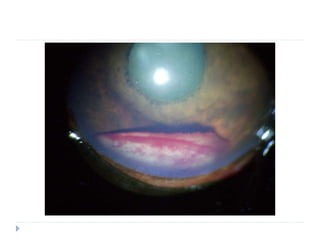

Signes spécifiques : hypopion

Specific sign : hypopion - Dog